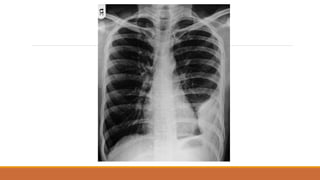

Thế thẳng trước ‐sau (A.P)